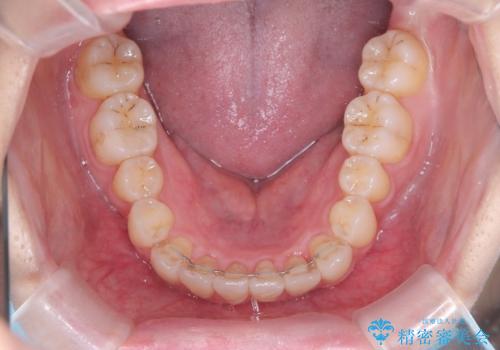

反対咬合を治したい。インビザライン

- 前歯の反対咬合を治したいことを主訴に来院されました。

インビザラインにて臼歯の遠心移動を行いながら、スペースを作り反対咬合を改善することができました。